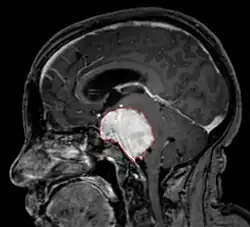

Imaging

• MRI

• Preferred imaging because it can show dural origin

• Dural tail sign seen in about two-thirds: characteristic marginal thickening that tapers peripherally along the dura

• Isointense on T1, hyperintense (usually homogeneously) on T2, strong enhancement with IV contrast